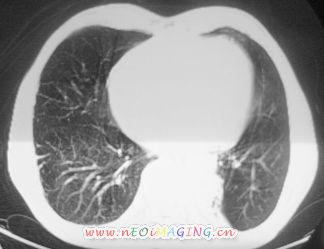

以下是引用卜一在2007-10-7 9:38:00的发言:[br]左下肺胸膜下团片影,内见含气支气管像,临近胸膜未见增厚。多考虑:1 左下肺炎症,建议消炎后复查!2 不除外肺隔离症合并感染!